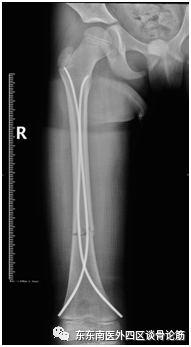

评估病情后,我科运用闭合复位弹性髓内针固定的微创技术对涛涛进行了手术治疗,将其断骨接上了。弹性髓内针可以做到闭合置钉,不仅可达到良好复位及良好固定的基本要求,还具有小切口微创置入,骨折处无需切开,对血供影响小,不破坏骨膜,不损伤神经,利于骨痂生长,完全符合儿童生理。这一微创治疗方式有效地降低了因手术创伤影响儿童骨折生长发育的风险。

(术后X线)